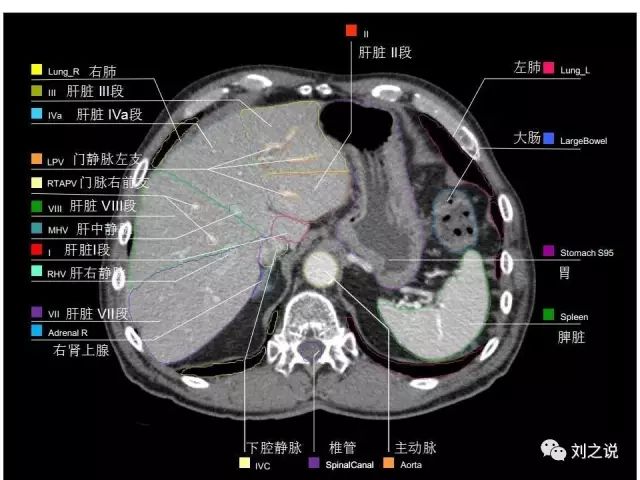

参考RTOG共识和3D-body解剖。

来源:刘之说